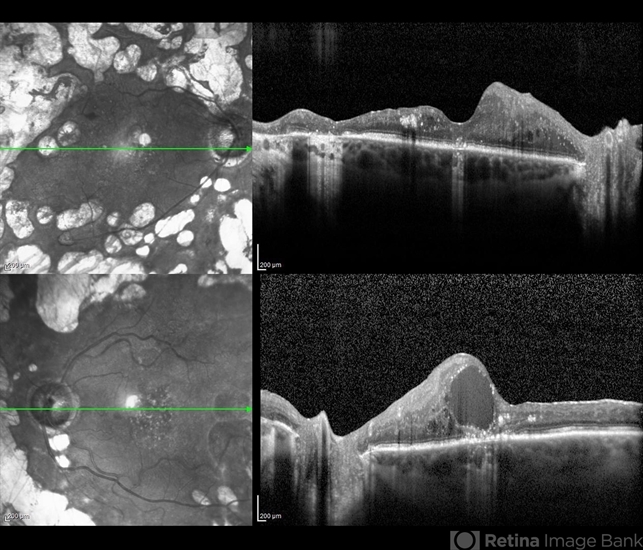

- optical coherence tomography (OCT), proliferative diabetic retinopathy (PDR), diabetic macular edema, glaucoma, edema, pan-retinal photocoagulation (PRP), anti-VEGF

- Optical coherence tomography of an 54-year-old female with diabetic macular edema affecting both eyes. Patient has a history of proliferative diabetic retinopathy s/p PRP/PPV/MP/EL, and glaucoma s/p tube shunt in both eyes. There has been a persistence of her macular edema and limited response to antiVEGF therapy, which puts into question whether there is another cause for her edema. Leading the possible causes is her renal insufficiency and fluid retention. Patient was seeing 20/50 in the right eye and 20/80 in the left eye.